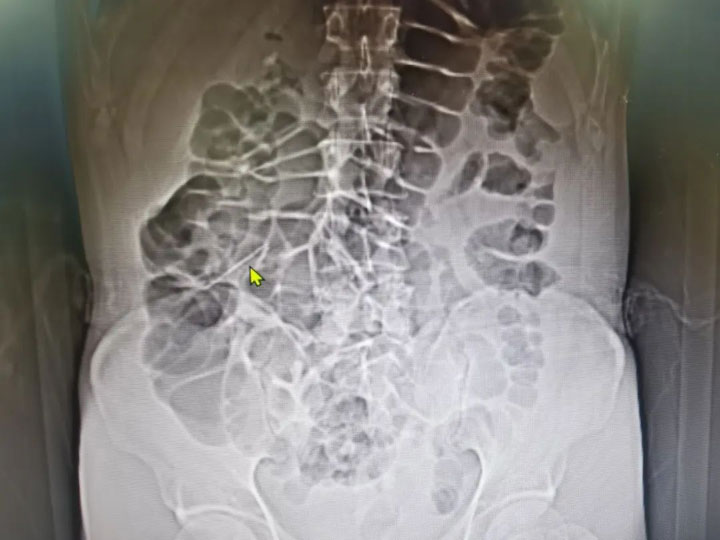

近日,50岁的孙师傅(化名)就诊广济医院,患者主诉反复腹痛半年余,体格检查后行腹部CT检查,提示:腹腔内异物。考虑到异物所在位置可能位于肠内,消化内科胡焕标主任为其行无痛肠镜检查,反复查看肠腔内情况,未见肠腔内黏膜异常病变,排除肠内异物。

为明确异物是否经过肠道已经排出,当即利用肠内残余气体,为其行腹部CT,发现异物仍在体内,考虑异物已穿至肠腔外,肠间隙之间。

急诊手术立即安排,普外科、麻醉科默契配合,发挥腹腔镜术式的微创优势,循迹查找,很快发现异物,顺利将异物完整取出——一枚“锈”花针。

“如果异物继续留在体内,就像一颗不定时炸弹,可能会继续损伤腹腔组织,造成感染恶化,严重甚至会威胁患者的生命安全。”主刀医生普外科代坤主任解释道:“患者异物穿至肠腔外,被组织包裹,伤及肠管浆肌层。幸运的是,异物虽然锈迹斑斑,但完整取出,没有断裂和残留,经过微创治疗,3天康复出院。”